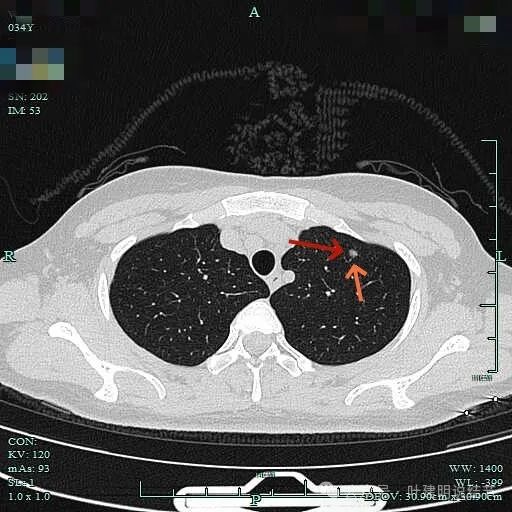

2、影像展示与分析:

轮廓清,有微小血管走向病灶,表面并不光滑。

灶内密度也不均匀,微小血管走向病灶。